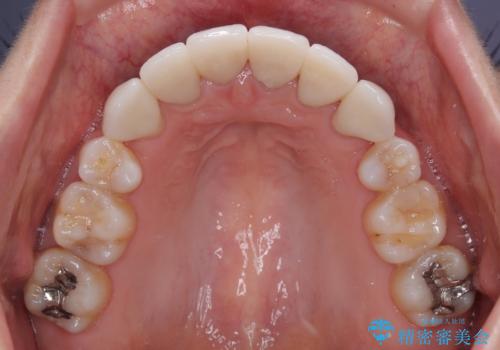

4本とも歯根部先端の骨が炎症により吸収していることがレントゲン写真から示唆されたため、矯正治療後に4本を再根管治療し、その後上顎6歯をオールセラミッククラウンにて補綴治療することとしました。

歯並びだけでなく、歯の色も明るくなり、すっきりとした口元の印象となりました。